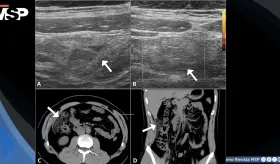

A pesar de los análisis normales, presentaba reserva ovárica baja y hallazgos ecográficos anormales. Durante la cirugía se descubrió daño severo en sus órganos reproductivos, con adherencias, trompas bloqueadas y destrucción del tejido ovárico.